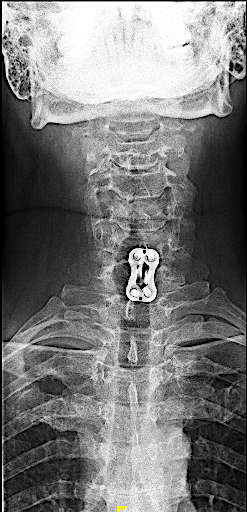

Obsérvese en la RX AP cervical que, tanto la caja intersomática como la placa, tuvieron que desplazarse ligeramente a la izquierda, donde había integridad de platillos. Dada la existencia de pseudoartrosis y destrucción de platillos, consideré oportuno reforzar la caja atornillada con una placa cervical.

Las RX dinámicas demuestran fijación intersomática sin puentes óseos todavía. Obsérvese la recuperación del espacio intersomático respecto al preoperatorio, (indicativo de estabilidad de la artrodesis). El paciente, a los 6 meses de la cirugía, refiere crisis frecuentes de cervicalgias mecánicas altas bien controladas con analgesia de primer nivel y reposo relativo (ha dejado mórficos) y resolución de la braquialgia izquierda.